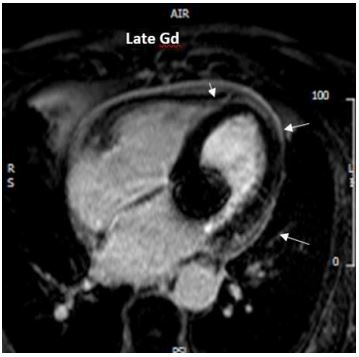

Figure 5: Cardiac magnetic resonance depicting pericardial Late Gadolinium Enhancement (LGE) and a small circumferential pericardial effusion.

Cardiac magnetic resonance finally confirmed the diagnosis of acute pericarditis, by demonstrating diffuse inflammation and oedema of the pericardium (Figure 4). Pericardial late gadolinium enhancement (LGE) was also detected (Figure 5).